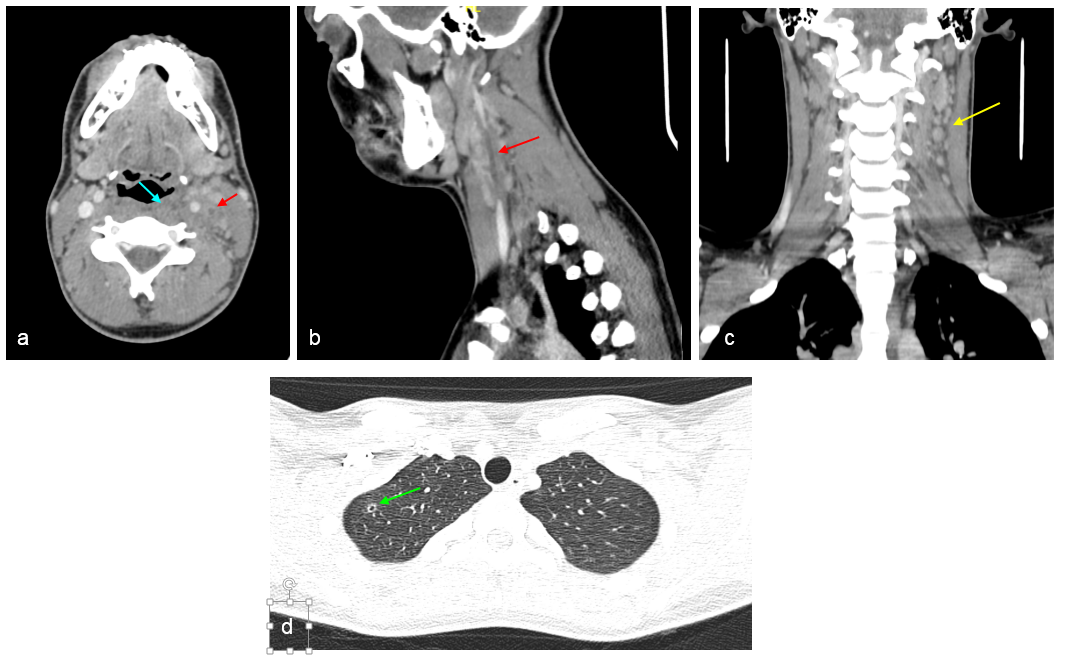

Imágenes de TC cervical con contraste en reconstrucciones axial (a), sagital (b) y coronal (c) y de TC pulmonar con contraste en axial (d).

Se identifica discreta tumefacción de amígdala palatina izquierda, sin colecciones evidentes, en relación con cambios inflamatorios de la misma (a, flecha azul). Falta de opacificación de la vena yugular interna izquierda compatible con trombosis (a y b, flechas rojas). Numerosos ganglios reactivos cervicales ipsilaterales (c, flecha amarilla).

Lesión nodular cavitada en segmento apical de lóbulo superior derecho pulmonar (d, flecha verde).

En el estudio mediante TC cervical con contraste se observan un defecto de repleción de la vena yugular interna (también evidenciable mediante estudio ecográfico), cambios inflamatorios del tejido graso adyacente y, en algunos casos, nódulos pulmonares cavitados en relación con las metástasis sépticas mencionadas.